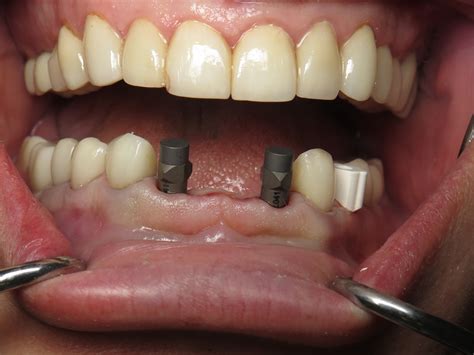

Implant Placement Surgical insertion of the titanium post into the jawbone.

Osseointegration A healing period of 3–6 months where the bone fuses to the implant.

Abutment & Crown Attaching the connector and the final, custom-made ceramic crown.

Another common concern is the "temporary" phase. Because the front area is visible, dentists often provide a temporary prosthetic (such as a flipper or a temporary crown) immediately after the surgery. This ensures that you do not have to walk around with a visible gap while the underlying bone and gum tissue heal.